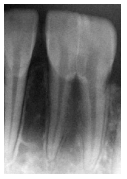

Em uma radiografia periapical de um indivíduo desconhecido, solicitada para fins de identificação odontolegal, observa-se um dente incisivo inferior com duas raízes separadas e com canais radiculares independentes; contudo, apresentando duas coroas fundidas parcialmente, ilustradas na imagem abaixo.

Com base nesses achados, assinale a alternativa que descreve corretamente as alterações dentárias observadas.